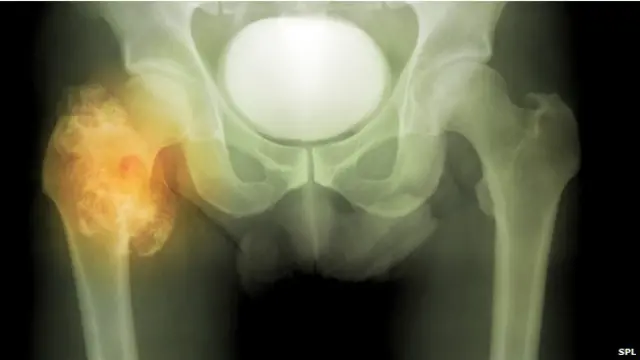

'बुरी किस्मत' से हो जाते हैं कई कैंसर

अधिकांश कैंसर धूम्रपान जैसी हानिकारक चीजों से नहीं बल्कि 'बुरी किस्मत' से हो सकता है. अमरीकी टीम के शोध में ये बात सामने आई है.

साइंस पत्रिका में प्रकाशित शोध के नतीजे बताते हैं दो-तिहाई प्रकार के <link type="page"><caption> कैंसर </caption><url href="http://www.bbc.co.uk/hindi/international/2014/09/140919_breast_cancer_angelina_effect_tk.shtml" platform="highweb"/></link>व्यक्ति की जीवनशैली की तुलना में केवल 'संयोगवश' से हो जाते हैं.

उनके अध्ययन का सार ये रहा कि दो-तिहाई तरीके के कैंसर स्टेम कोशिकाओं के विभाजित होने और म्यूटेशन से प्रभावित होने से होते हैं, जिसे एक बुरा संयोग ही माना जा सकता है.

बुरे संयोग से होने वाले कैंसर में मस्तिष्क कैंसर, छोटी आंत का कैंसर और पैनक्रियाज़ के कैंसर शामिल हैं.